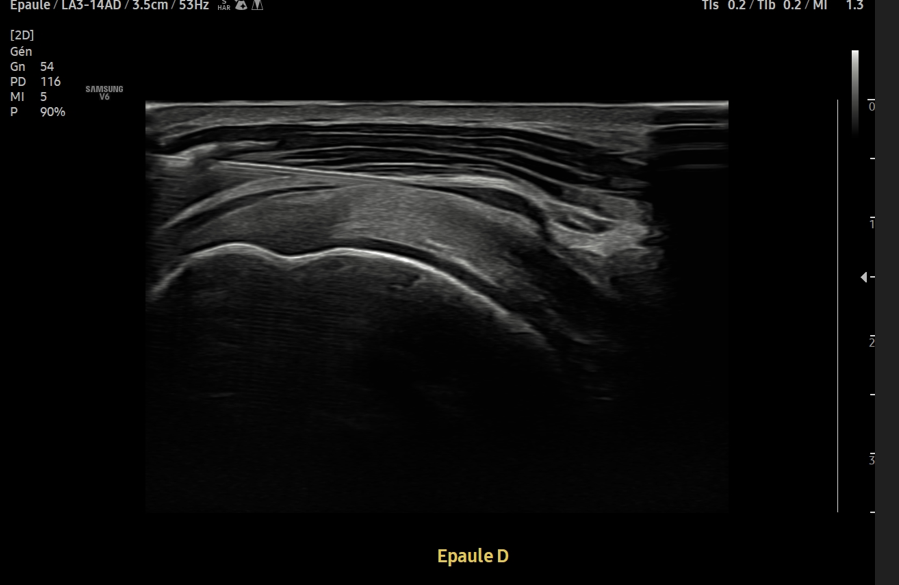

Consent ✅

F 60s

Years of diffuse R gluteal, hip & thigh pain, constant, stairs & sitting aggravates

Seen by orthopaedics to evaluate hip & knee (previous patellectomy this side) - referred to me as unable to identify pain driver & MRI scans 'normal'

MRI pelvis - hip joints & lateral soft tissues are fine

Clear suspect for her pain though, even on first glance - what do you see?